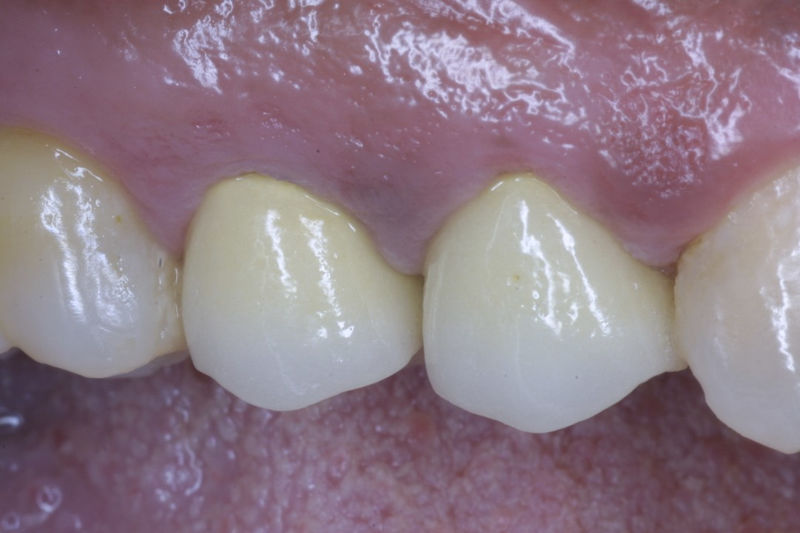

Son restauraciones que cubren toda la cara frontal del diente, generalmente empleadas en el sector anterior y cuya finalidad es primariamente estética.

Restauraciones fabricadas en el laboratorio con materiales estéticos, los cuales cubren de manera total dientes anteriores y posteriores. Se utilizan primariamente para restaurar dientes con caries, fracturas y/o defectos amplios, así como soportes de puentes. Para poder enviar el caso al laboratorio se toman impresiones utilizando materiales de impresión o técnicas modernas digitales.